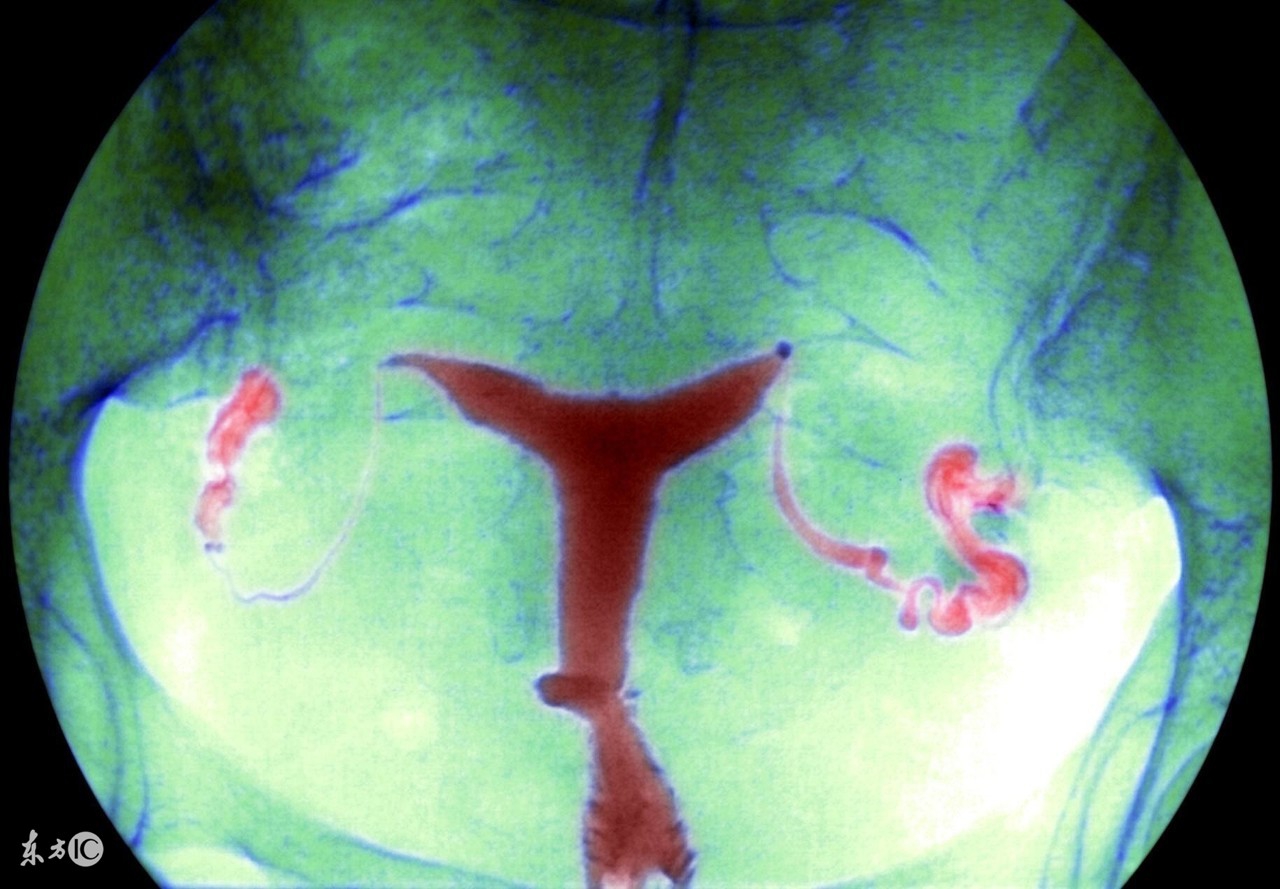

盆腔炎是女性常见的一种疾病,可分为慢性和急性。生活中,慢性盆腔炎比较常见,这种病在病发时可能会伴随着一些低热,病人会觉得自己总是感到疲劳,但是由于全身上下的症状并没有很明显,所以难以引起关注。

慢性盆腔炎可能会引起下腹坠痛,这是盆腔出血或者瘢痕粘连导致,特别是在女性在劳累,月经前后情况会有所加剧。在生活中不乏有女性因为慢性盆腔炎的诊治不及时,最后导致了不孕不育。如果想要预防盆腔炎,就需要做到以下几点: